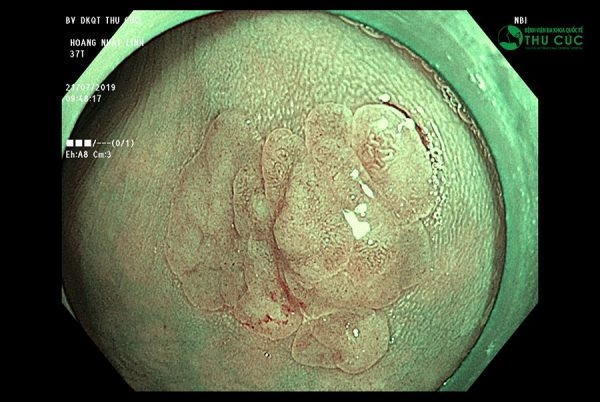

Không chỉ êm ái nhẹ nhàng, công nghệ nội soi NBI 5P tại Thu Cúc còn có khả năng phát hiện sớm ung thư và các bệnh lý tiêu hóa ngay từ khi còn rất sớm nhờ sử dụng dải tần ánh sáng hẹp với 2 bước sóng 415nm và 540nm. Điều này cho phép nội soi NBI quan sát sắc nét dưới lớp niêm mạc từ đó phân tích hình ảnh tập trung cao ở những vùng thiết yếu, phát hiện các biến đổi ở lớp bề mặt niêm mạc ống tiêu hóa và hệ thống mao mạch nông nuôi dưỡng lớp niêm mạc, phát hiện sự tăng sinh bất thường của hệ vi mạch máu nông ở vị trí khối u.

Công nghệ này cũng có khả năng phóng đại hình ảnh lên đến hơn 100 lần nhờ ứng dụng công nghệ Dual Focus hiện đại nhất thế giới, cho phép ống soi tiếp cận vị trí tổn thương ở khoảng cách gần nhất (từ 2 đến 6mm). Nhờ đó bác sĩ có thể phát hiện các tổn thương, khối u, tổ chức tiền ung thư ngay từ khi mới khởi phát. Đây là ưu điểm mà các công nghệ nội soi trước đó không có được.

Công nghệ nội soi NBI 5P có khả năng phát hiện ung thư tiêu hóa